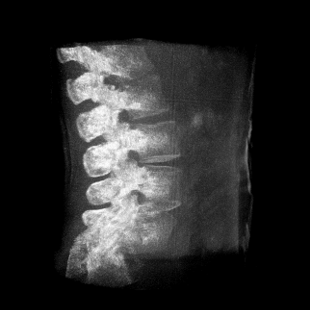

提供更大的術(shù)中三維成像視野,采集更多圖像信息,可一次拍全全段頸椎、全段腰椎、七節(jié)胸椎、雙側(cè)骶髂關(guān)節(jié)、股骨頭及單側(cè)盆骨。

在C臂掃描過程中,始終保持拍攝主體處于射線束的中心,避免了序列圖像采集過程中的橫縱方向運動,減少相對運動造成的運動偽影。